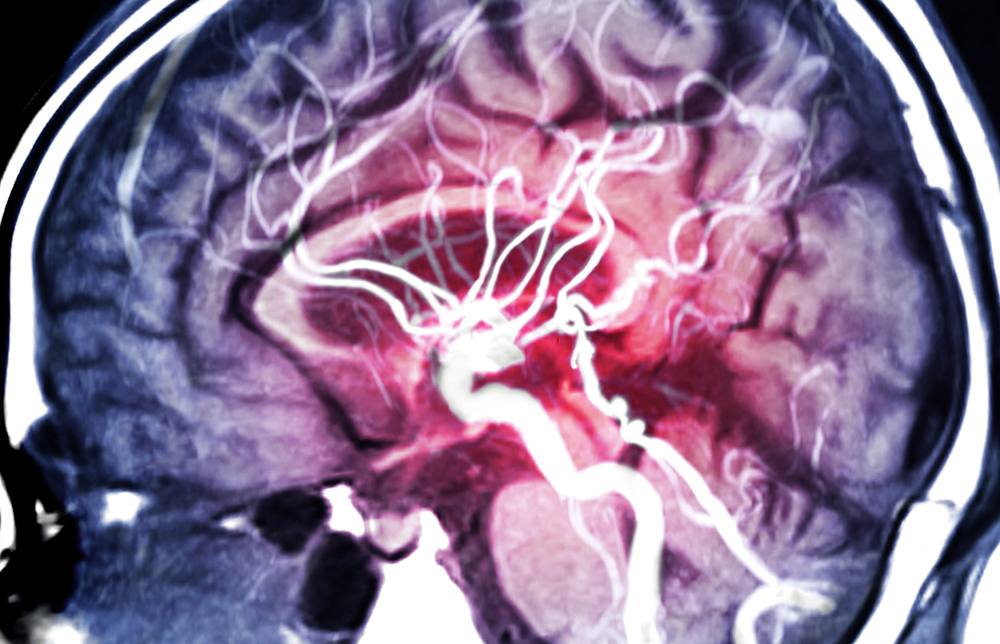

Strokes are classified as either ischemic or hemorrhagic. Approximately 85% of all strokes are ischemic; those strokes occur when a blood clot or built-up plaque blocks a blood vessel, preventing blood flow to part of the brain. Hemorrhagic strokes happen when a blood vessel or aneurysm ruptures in the brain, causing bleeding in the brain and damage to brain cells.